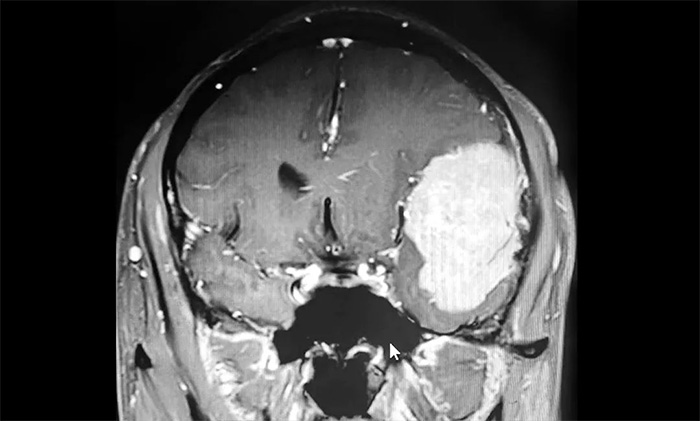

大年初四,由神經(jīng)外科6B病區(qū)特需專家顧國(guó)山教授主刀,成功切除一例11cm巨大矢狀竇旁腦膜瘤。術(shù)中還采用了全新的自體血液回輸技術(shù),為手術(shù)安全、高效的開展,提供了有力保障。...[詳細(xì)]

1月26日,神經(jīng)外科顧國(guó)山教授順利完成一例巨大腦膜瘤切除手術(shù)。患者術(shù)后恢復(fù)良好,日前已康復(fù)出院。...[詳細(xì)]